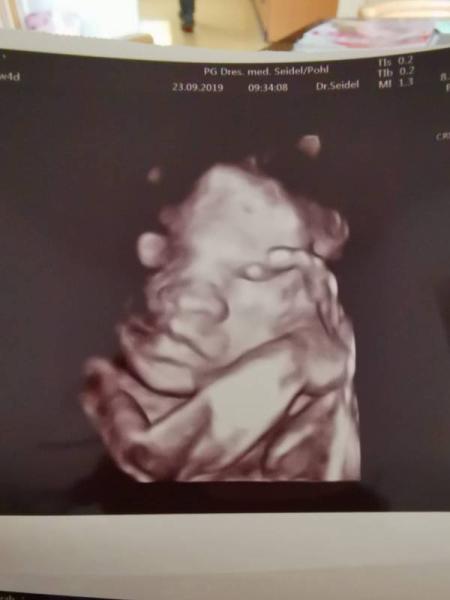

Auf heute habe ich mich echt mega gefreut, endlich hatte ich wieder Untersuchung und wir haben gleich den Zuckertest gemacht. Muss noch ein paar Minuten warten, dann wird mir Blut abgenommen und falls was ist, bekomme ich morgen Bescheid. Aber erstmal zur Untersuchung, der Maus geht es richtig richtig gut. Alles super entwickelt, hat und heute auch zu 100 % das Geschlecht gezeigt. Bleibt zum Glück beim Mädchen Heute wollte sie ihre Hände zeigen und immer schön gewunken sie wiegt jetzt 800 Gramm, was ich natürlich schon sehr merke. Bin so froh das es ihr richtig gut geht.

Bild zu Heute endlich wieder Termin gehabt - Forum für Januar - Mamis